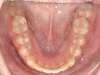

Chevauchement sévère. Traitement multibague sans extraction.

Avant

Après